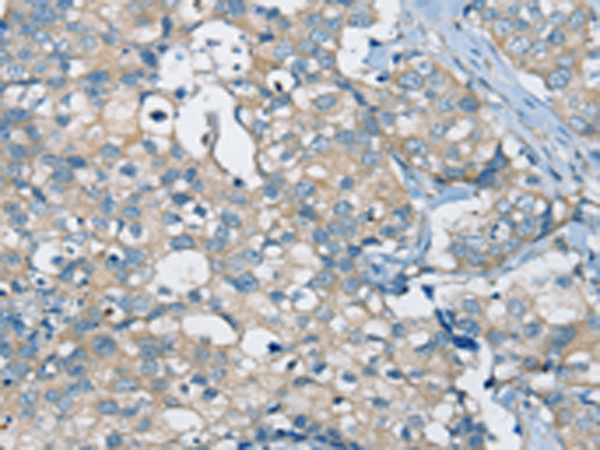

分类: 科研抗体货号: P12181别名: NCKX3应用: IHC反应种属: Human, Mouse, Rat